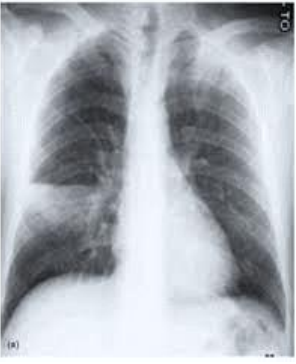

Paciente do sexo masculino, 52 anos, hipertenso e com hipotireoidismo, em tratamento regular, comparece à UBS onde você está atuando com queixa de tosse produtiva de 7 dias e evolução associada a quadro febril que se iniciou há 5 dias. Nega internações prévias. Ao exame físico, apresenta-se em regular estado geral, febril, acianótico, Glasgow 15/15. Ausculta pulmonar: murmúrio vesicular conservado com estertor crepitante em terço médio do pulmão direito. Ausculta cardíaca: BRNF 2T. Abdômen: flácido, hiper-timpânico RH presentes. Sinais vitais: FC 105; FR 25; temperatura axilar: 38,1; SatO2 96%; PA 115/70. O paciente possui exames laboratoriais realizados no dia anterior, assim como radiografia de tórax, apresentada a seguir. Leucócitos 14800 MM3; neutrofilos 85%; bastões 5%; PCR quantitativo 18mg/dl; ureia 55 mg/dl; Creatinina 1 mg/dl.

Enunciado 3123707-1

Assinale a alternativa que apresenta a conduta adequada frente ao caso clínico exposto.